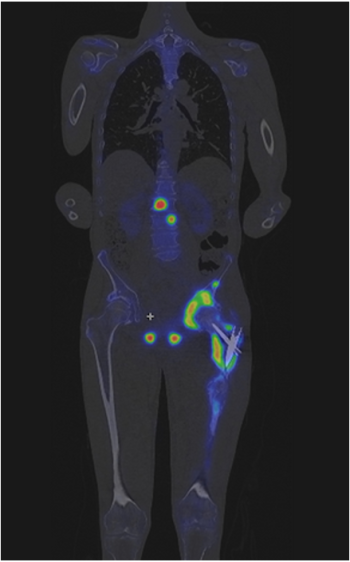

IV.4.6. SPECT – A szcintigráfiatomográfos alkalmazása

- IV.4. Nukleáris diagnosztika